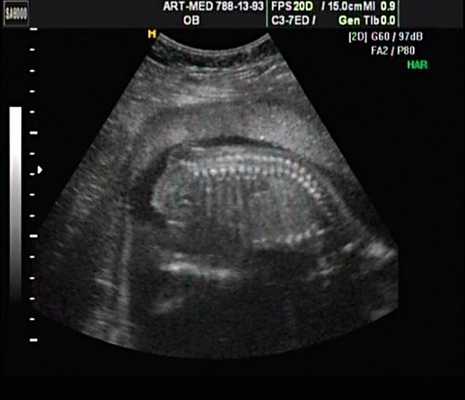

Пациентка К., 26 лет, обратилась в клинику в 23 нед беременности. Беременность первая. Исследование проводилось на аппарате Accuvix-XQ (Samsung Medison) с использованием режима поверхностной объемной реконструкции 3D/4D. Показатели фетометрии полностью соответствовали сроку беременности. В процессе сканирования позвоночника во фронтальной и сагиттальной плоскостях выявлена угловая деформация позвоночника в грудном отделе, протяженностью около трех позвонков. В поперечной плоскости сканирования нарушения структур и целостности тканей не было обнаружено. В режиме 3D/4D реконструкции было выявлено асимметричное расхождение ребер правой и левой стороны грудной клетки (рис. 4).

Рис. 4. Эхографическая картина асимметрии ребер в режиме 3D реконструкции.

Ребра левой стороны были сближены, межреберные промежутки уменьшены по сравнению с противоположной стороной (рис. 5, 6). Другой патологии у плода не было выявлено. Заподозрен врожденный сколиоз, основой которого является наличие боковых полупозвонков (hemivertebrae) или боковых клиновидных позвонков. В 26 нед ультразвуковая картина сохранялась. При проведении трехмерной эхографии получено отчетливое изображение асимметрии реберных дуг и сколиотическая деформация позвоночника.

Рис. 5. Асимметрия межреберных промежутков в режиме 3D реконструкции.